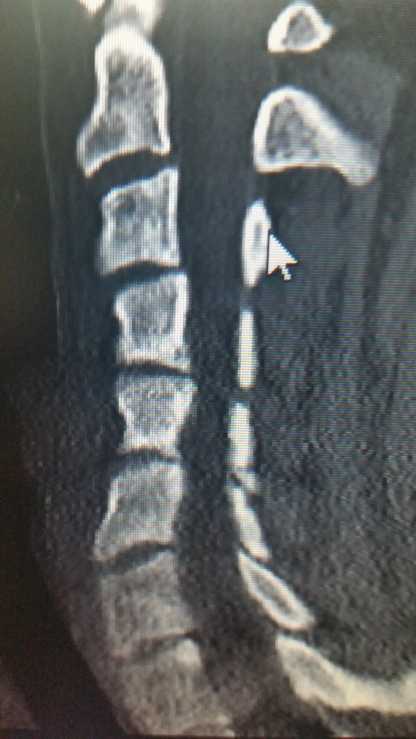

So today I saw my 'new' pain specialist. I say new but I've been a coworker of his for 3 years. He took one look at my cervical CT and shuddered. 3 neurosurgeons and a spinal surgeon and a different pain specialist ALL said my neck looked fine. ...